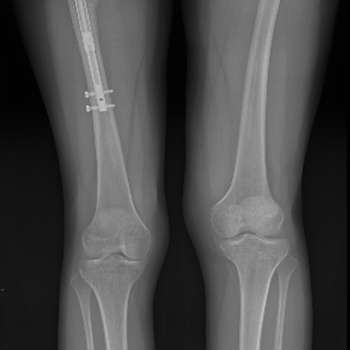

con clavo Precice

con clavo Precice

El equipo, formado por los Dres. Javier Alonso, Juan Cabello y Carlos Miranda, ha llevado a cabo con éxito más de 30 procedimientos quirúrgicos de Alargamiento con clavo intramedular en Madrid, siendo el equipo que más experiencia tiene en España y uno de los grupos con más experiencia en Europa.

El nuevo clavo Precice es el dispositivo de alargamiento más avanzado disponible en la actualidad. El clavo Precice tiene un excelente control de la tasa de alargamiento y los pacientes que han sido tratados mediante ambas técnicas (precice vs fijador externo) refieren una disminución significativa del dolor y discomfort.